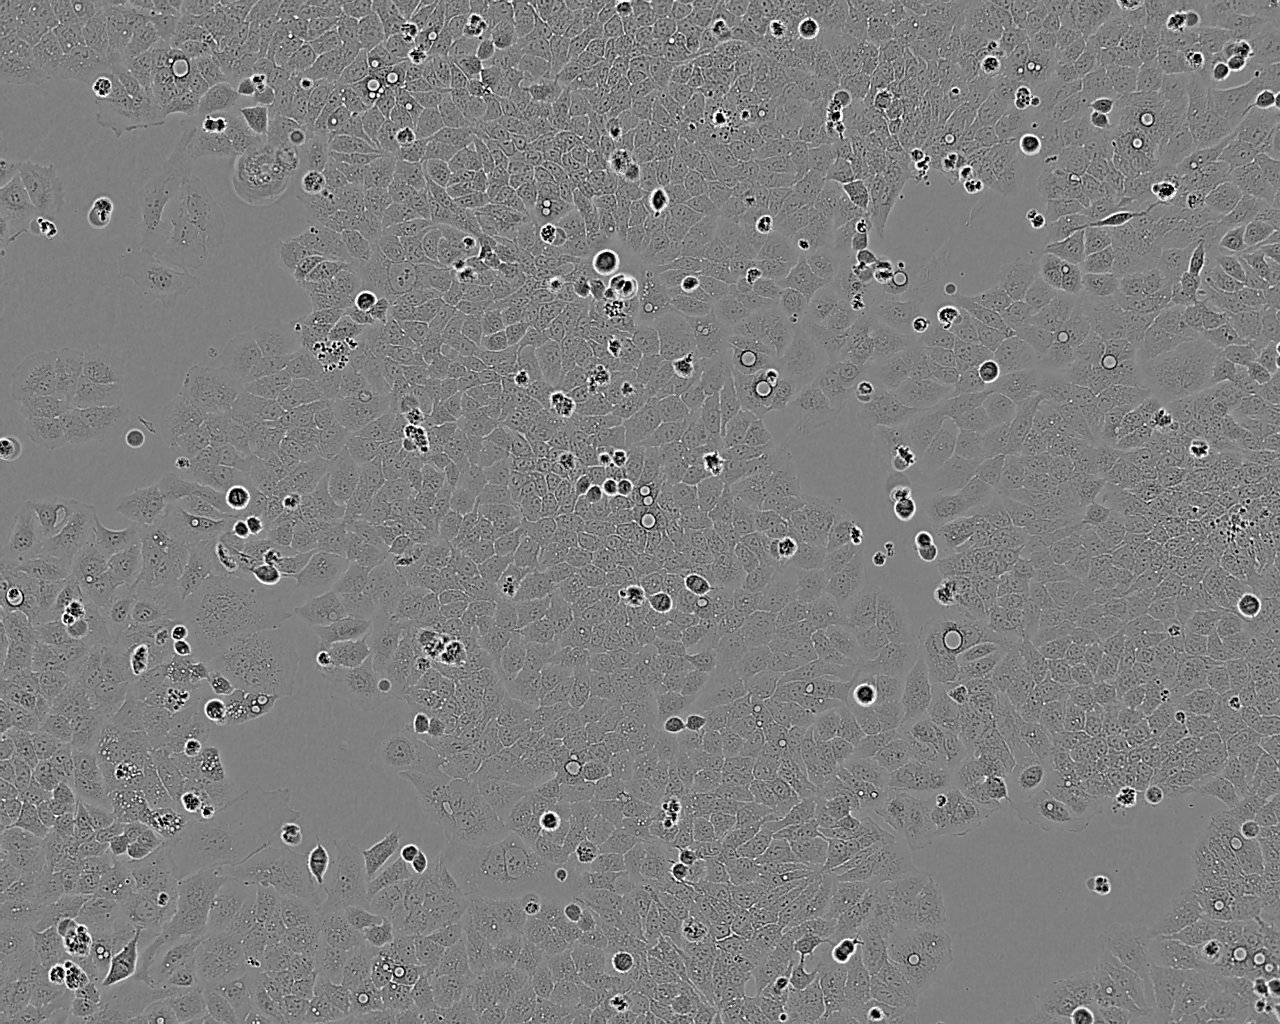

细胞背景资料:脑瘤;女性

细胞形态:上皮细胞样

细胞生长:贴壁

细胞生长特性:贴壁